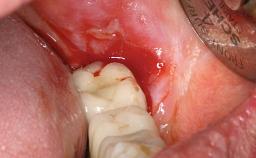

A 66-year-old patient presented because of retention loss of the tooth-supported FDP in the right maxilla (x-13-x-11). The mandibular full-arch implant-supported reconstruction (x-i34-i33-x-x-x-x-i43-i44-x) had suffered extreme wear. His medical history revealed high blood pressure, controlled with anti-hypertensive medication. The patient was a light smoker (2 to 3 cigarettes per day). The existing reconstructions had been performed alio loco about five years previously. That treatment had taken an extensive amount of time, and as early as during the fabrication of the reconstructions, multiple complications had occurred with the provisionals.